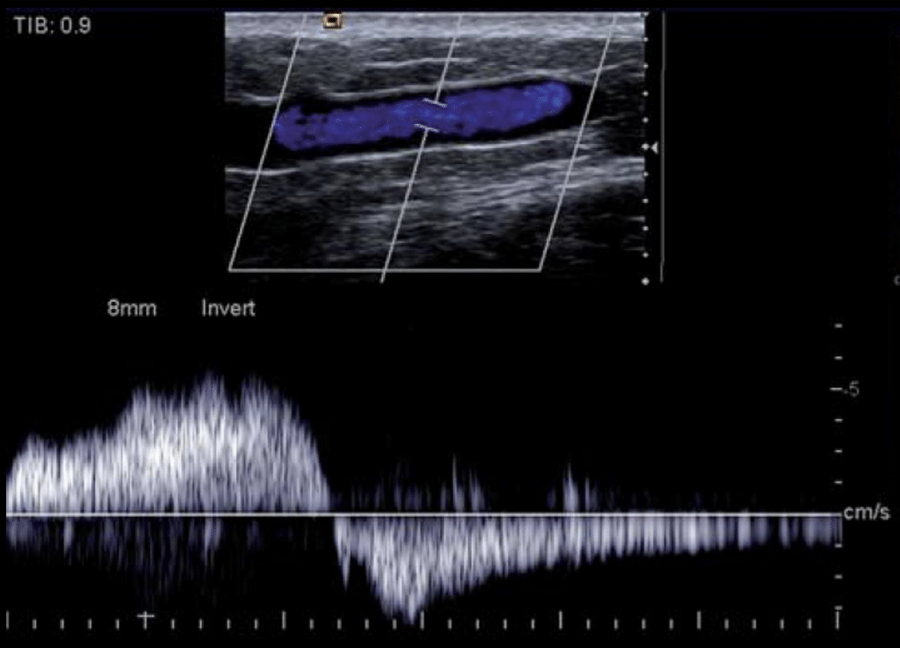

¿Onda anormal o trifásica?

Anormal

16

Q

A

x = tiempo (segundos)

y = velocidad (cm)

positivo = por encima de la línea

negativo = por debajo de la línea